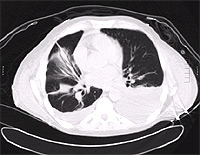

CT showing “crazy paving pattern in lower loges